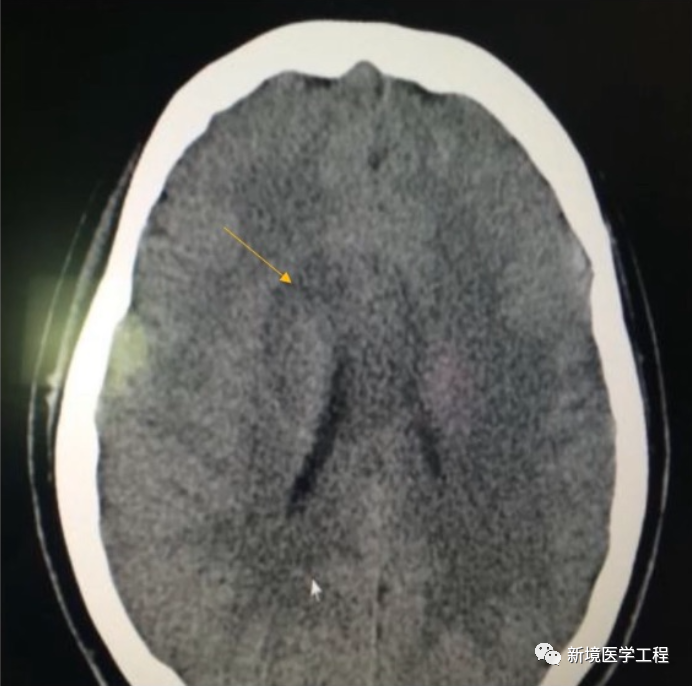

2.4「圆形伪影」

【产生原因】

温湿度变化较大,或长时间未进行空气矫正。

【解决办法】

执行空气矫正,用最新的矫正表重建图像。